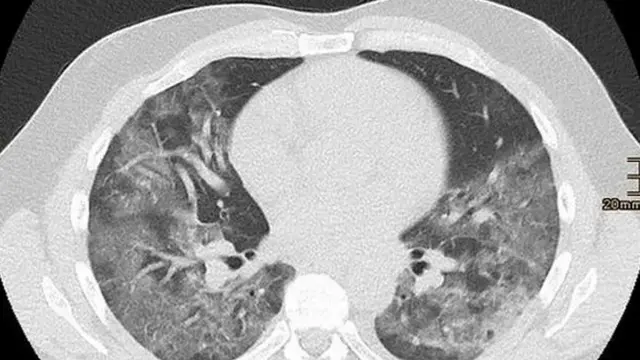

Apa yang ditemukan juga dari pemindaian melalui CT scan - prosedur yang menggunakan sinar X, dengan hasil yang diolah dengan komputer - lebih dari setengah pasien asimtomatik memiliki gejala kerusakan paru-paru serius.

Data dari penumpang kapal pesiar, menunjukkan 54% dari 76 pasien tanpa gejala, memiliki kerusakan paru-paru yang ditunjukkan melalui CT scan.

Gambar paru-paru yang pekat menunjukkan organ ini penuh dengan cairan, bakteri atau sel kekebalan.